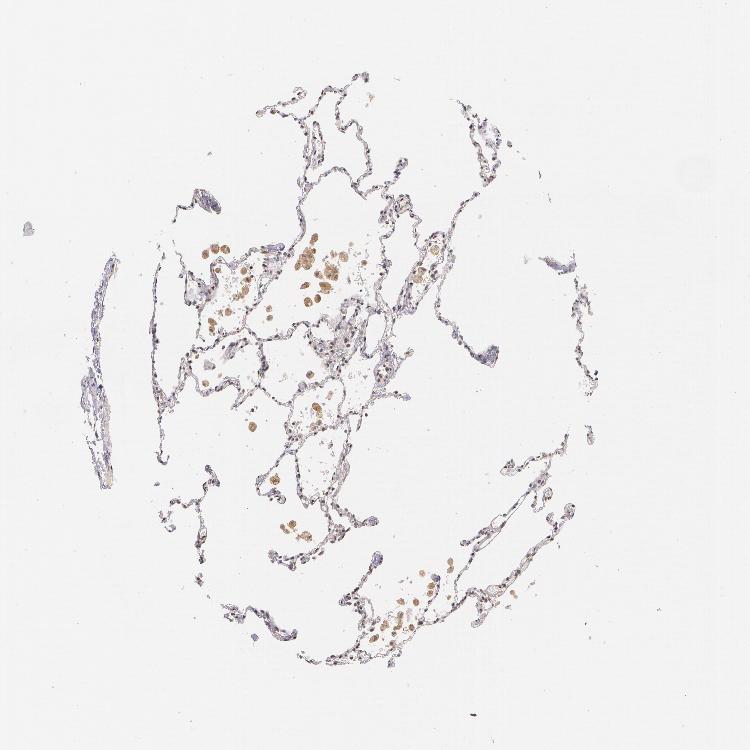

LUNG - Antibody stainingi

Antibody staining in the annotated cell types in the current human tissue is reported as not detected, low, medium, or high, based on conventional immunohistochemistry profiling in selected tissues. This score is based on the combination of the staining intensity and fraction of stained cells.

Each image is clickable and will lead to virtual microscopy that enables deeper exploration of all samples and also displays staining intensity scores, fraction scores and subcellular localization as well as patient and tissue information for each sample.

Antibody CAB002012

Alveolar cells Low

Macrophages Medium